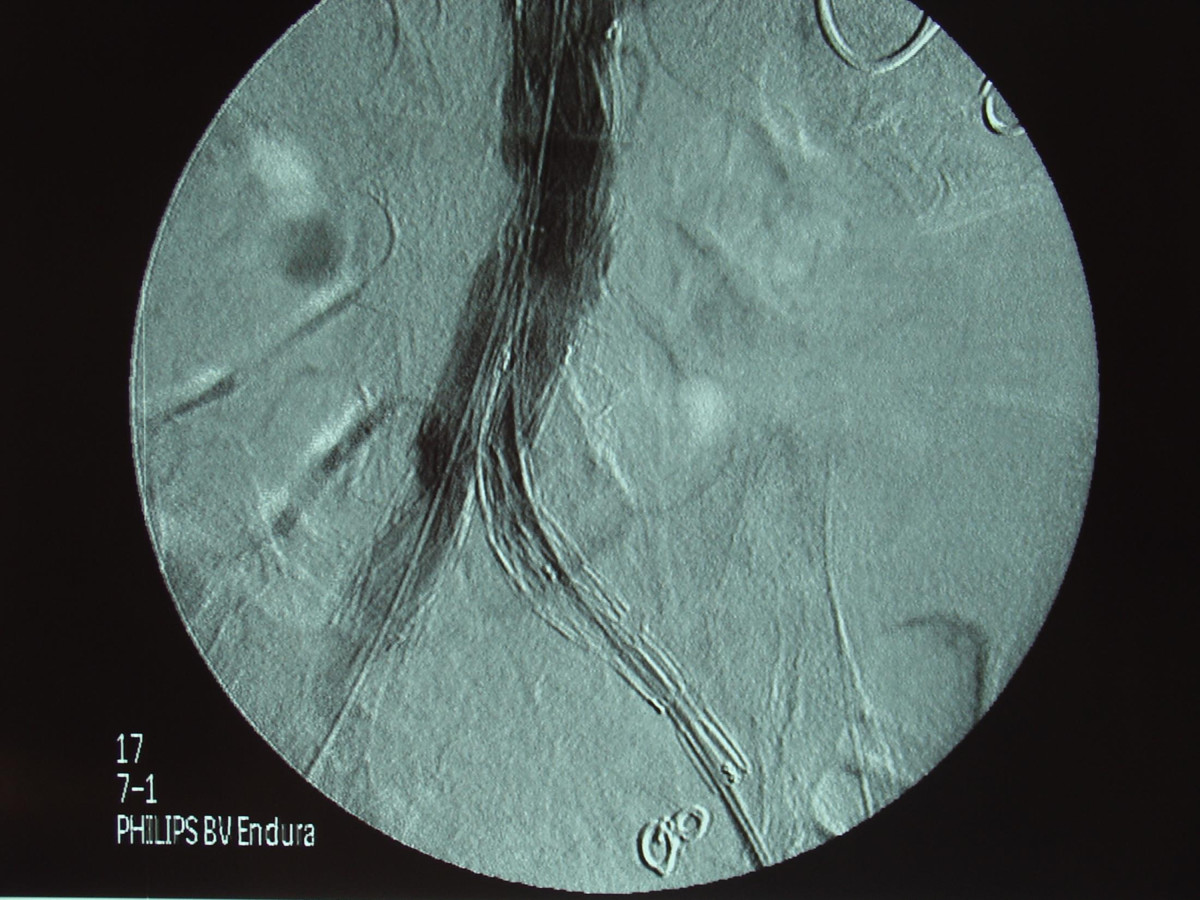

Ενδαγγειακή αποκατάσταση ανευρυσμάτων κοιλιακής αορτής

12ο Πανελλήνιο Συνέδριο Αγγειακής και Ενδαγγειακής Χειρουργικής

2010, Αθήνα